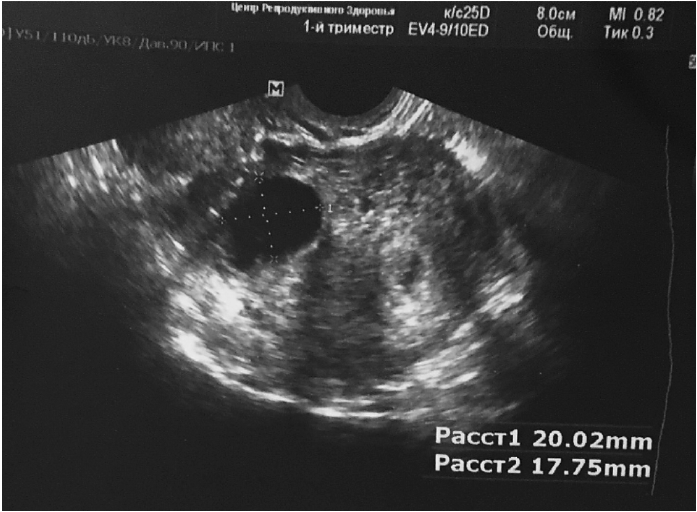

В октябре 2016 г. при УЗИ тела матки обнаружена кистозная анэхогенная полость с четким контуром диаметром 10 мм в толще миометрия задней стенки матки в первую фазу менструального цикла, которая увеличилась до 20 мм в динамике к июню 2017 г. на фоне лечения диеногестом 2 мг/сут в непрерывном режиме (рис. 1).

Рис. 1. Узловая форма аденомиоза.

Fig. 1. Nodular form of adenomyosis.